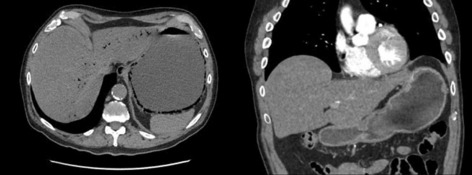

O258—Liver 3D printed mold for training in liver ultrasound guided procedures – concept and development

Introduction and background: In the twenty-first century, the rapidly evolving technological environment and the steep progress of medical science made the intraoperative ultrasound examination a mainstay for the correct and complete surgical treatment.

Hence, there is no interventional and diagnostic liver ultrasound specific training program in the surgical residency curriculum. Thus, the development of an experimental training model ment for interventional liver ultrasound became a necessity.

By using the already widespread 3D printing technology, we created a reproducible, low cost, multiple usage experimental liver model adapted to this purpose.

Materials and methods: By using a liver’s CT scan 3D virtual reconstruction, we have created a 3D live size virtual liver mold subsequently transformed into a real mold by 3D printing it with the FDM (fused deposition modelling) technology.

In this mold we have cast various liver models using several solution recipes with gelatin and liquid silicone for the liver parenchyma whereas for the liver tumors we added special dyes. With the gelatin based tumors we used wheat flour, talcum powder and corn starch for ultrasonographic contrast. All the models were analyzed for manufacturing time, cost, fiability, ultrasonic morphological testing and elastography.

Results: We conceived and made one model of 13 Shore hardness scale silicon model and three different concentrations gelatin models.

The silicon model is more expensive to manufacture, it is easier to handle but it has a hardness and a resilience to punctures too important for the purpose. It can probably be softened with the addition of siliconic oils, with the disadvantage of increasing the cost.

The gelatin models are more brittle and less long lasting but do have a stiffness closer to the cirrhotic liver (about 40 kPa for the intermediate model). The costs of the silicon model compared to gelatin model are 1:10. The higher concentration gelatin model behaves perfectly for handling as well as ultrasound-guided punctions.

Conclusion: The gelatin models with intermediate and higher stiffness proved to be the most fiabile for training in interventional liver ultrasound.